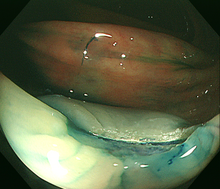

2)内視鏡的粘膜切除術(EMR)

大腸にできた小さな腫瘍やポリープが平坦または陥凹した形の場合、ポリープにスネアが掛かりにくいため、粘膜下に生理食塩水などを注入して隆起させ切除します。切除する病変の大きさや形状によりますが、1日から数日間の入院が必要です。

3)内視鏡的粘膜下層剥離術(ESD)